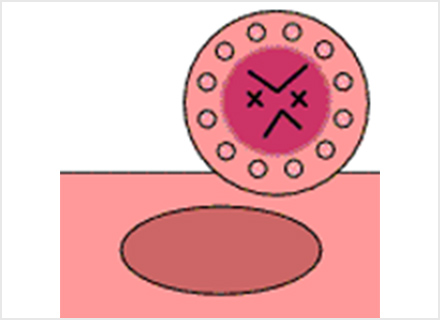

内視鏡的粘膜下層剥離術:ESD(Endoscopic submucosal dissection)

専用の処置具を使いより広範囲に病変を切り取ることが可能な治療法です。切り取られた病変は、最終的に顕微鏡でその組織の様子が確認されます(病理検査)。この方法では、大きな病変をひとかたまりで取り、病理検査でより正確な診断を行うことができます。

ESDは大きな病変も一括して切除可能ですが、手技が煩雑で時間がかかり、出血や穿孔などの併発症が生じる場合があります。ほとんどの場合内視鏡的に止血可能ですが、稀には輸血、開腹手術などを要することがあります。

切り取った後の胃の表面に止血処置を施し、切り取った病変部は病理検査に出すために回収する

切り取った病変は顕微鏡による組織検査をして、根治しているかの判断をする

※オリンパス社ホームページ おなかの健康ドットコム より引用